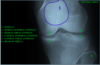

1

talus

2

navicular

3

calcaneus

4

cuboid

5

base of 1st metatarsal

6

head of 1st metatarsal

7

shaft of proximal phalyx of big toe

8

shaft of distal phalyx of big toe

asterisks

sesamoid bones

9

shaft of 5th metatarsal